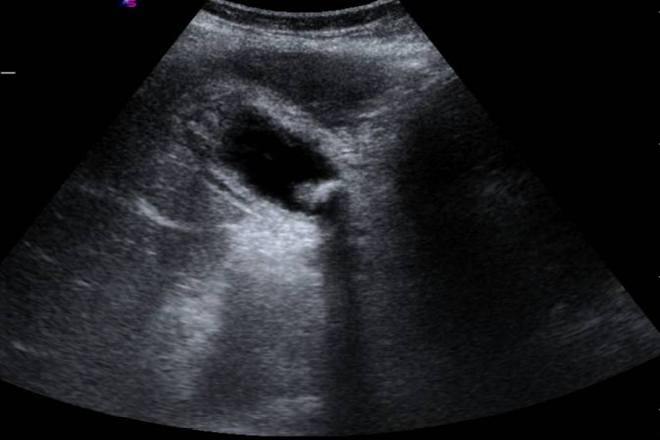

La ecografía es el método de elección actual para diagnosticar cálculos biliares, demostrando alta precisión diagnóstica (90 % de sensibilidad y 88 % de especificidad).

Los signos radiológicos de la colecistitis aguda incluyen engrosamiento de la pared vesicular (más de 4 mm), vesícula agrandada (diámetro eje largo mayor a 8 cm, eje corto mayor a 4 cm) o presencia de líquido alrededor de la vesícula.